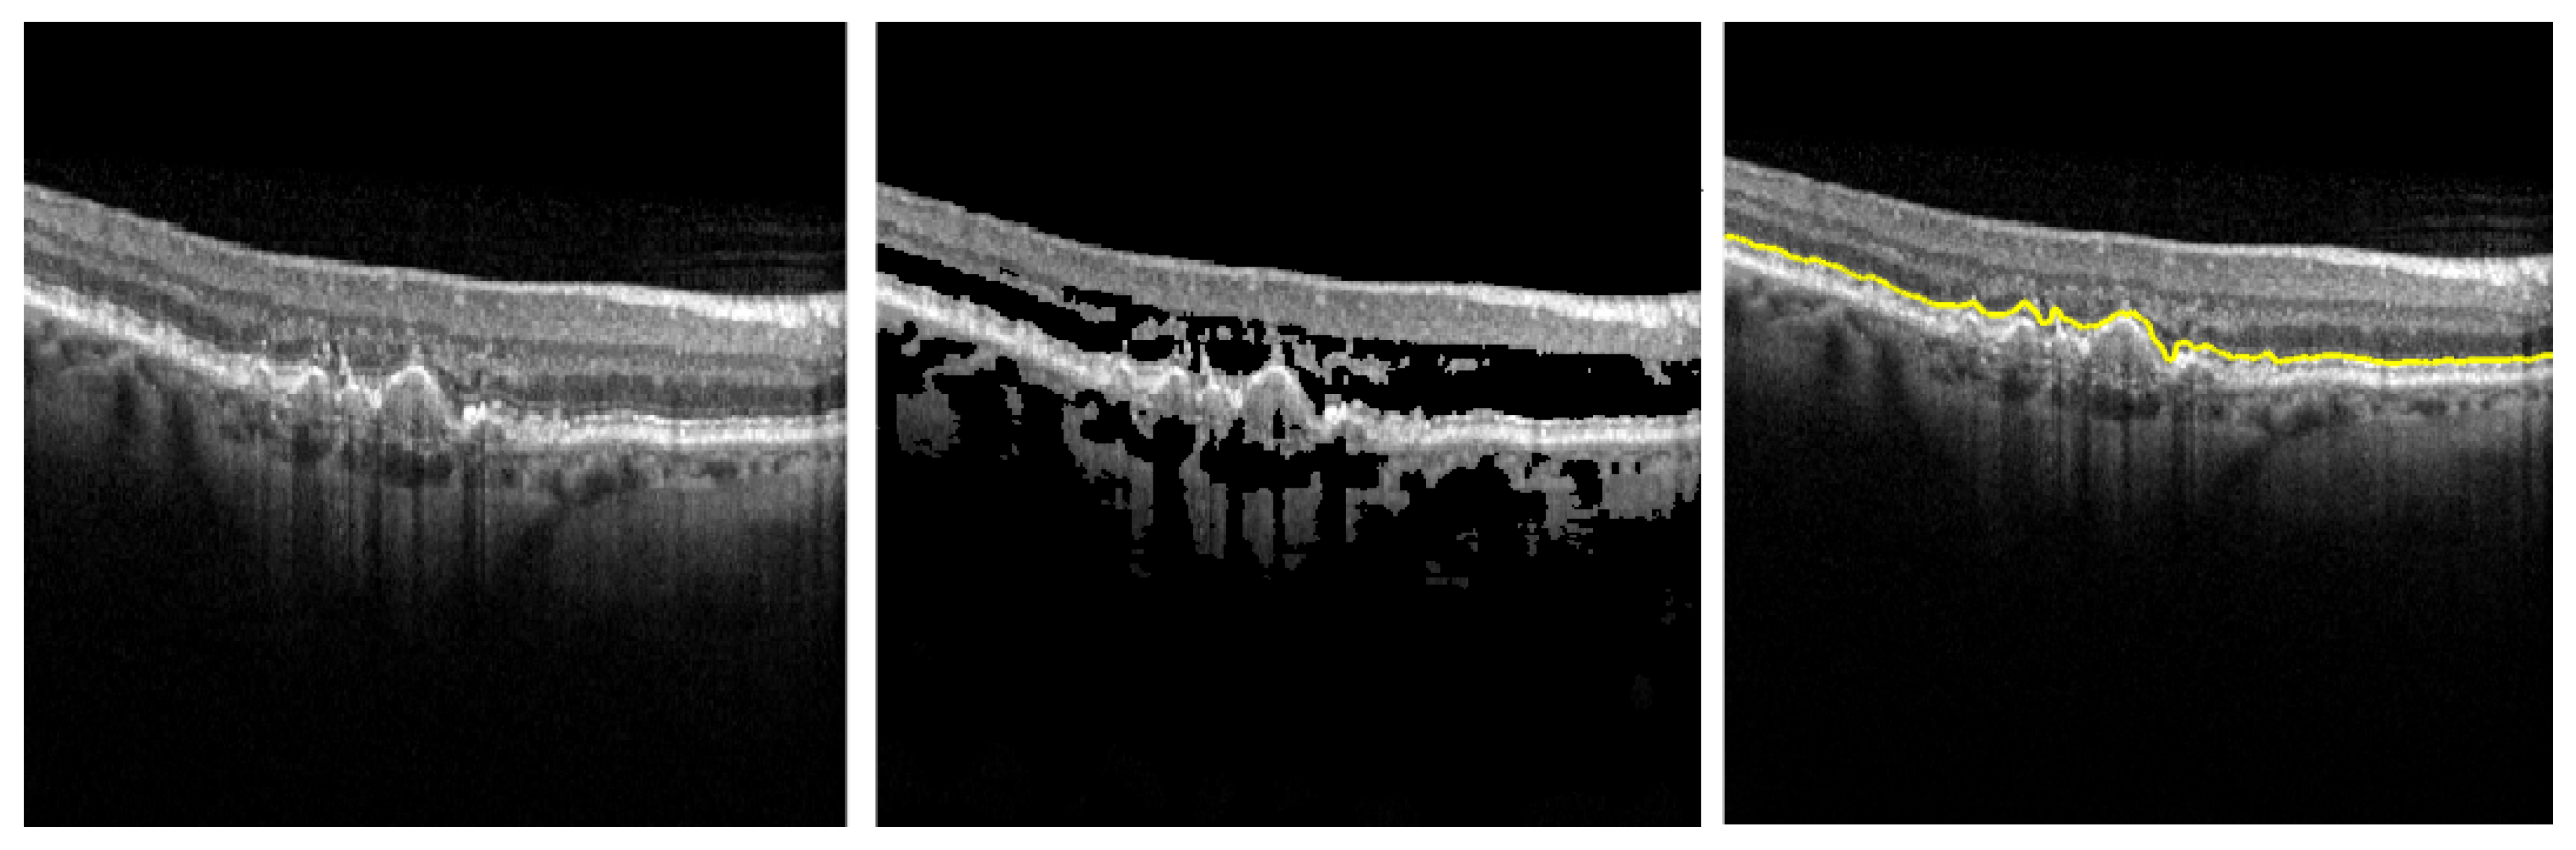

Since identifying the frontier between IS and OS layers is the key element in our approach (as the other layers depend on it), we need to assure its correctness. Our assumption is that following this adaptive thresholding algorithm, the highest intensity variation is on the IS-OS layer. Figure 2 bears this out. The system displays to the ophthalmologist only this layer (i.e., B7), in order for the human agent to check the validity of the segmentation (see Figure 3).

Figure 2. Modifying the initial OCT image (left) with an adaptive thresholding algorithm based on Equation (1) (center) aiming to accurately detect the easiest frontier between the IS and OS layers (right).

Diagnostics 12 00022 g002

Figure 3. Example of the segmentation of the IS-OS boundary before and after the correction of the segmenting parameters.

Diagnostics 12 00022 g003